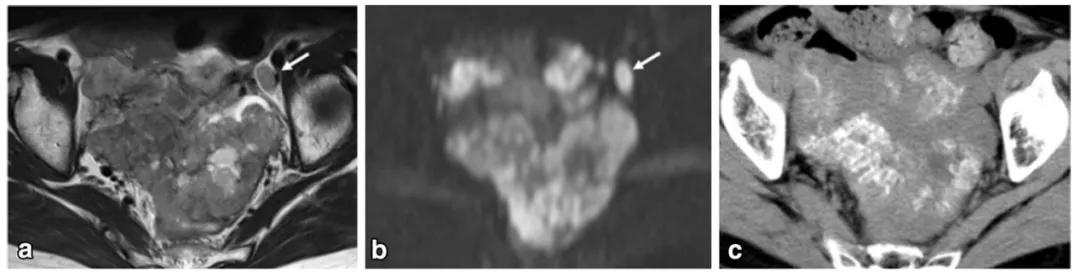

女,75 岁,浆液性癌。CA-125 升高。双侧卵巢不规则肿物,与腹膜结节分界不清,T2WI 呈不均匀稍高信号(图 a),DWI 呈不均匀高信号(图 b),CT 显示肿物内钙化(图 c)。箭头显示左侧髂血管旁转移淋巴结。